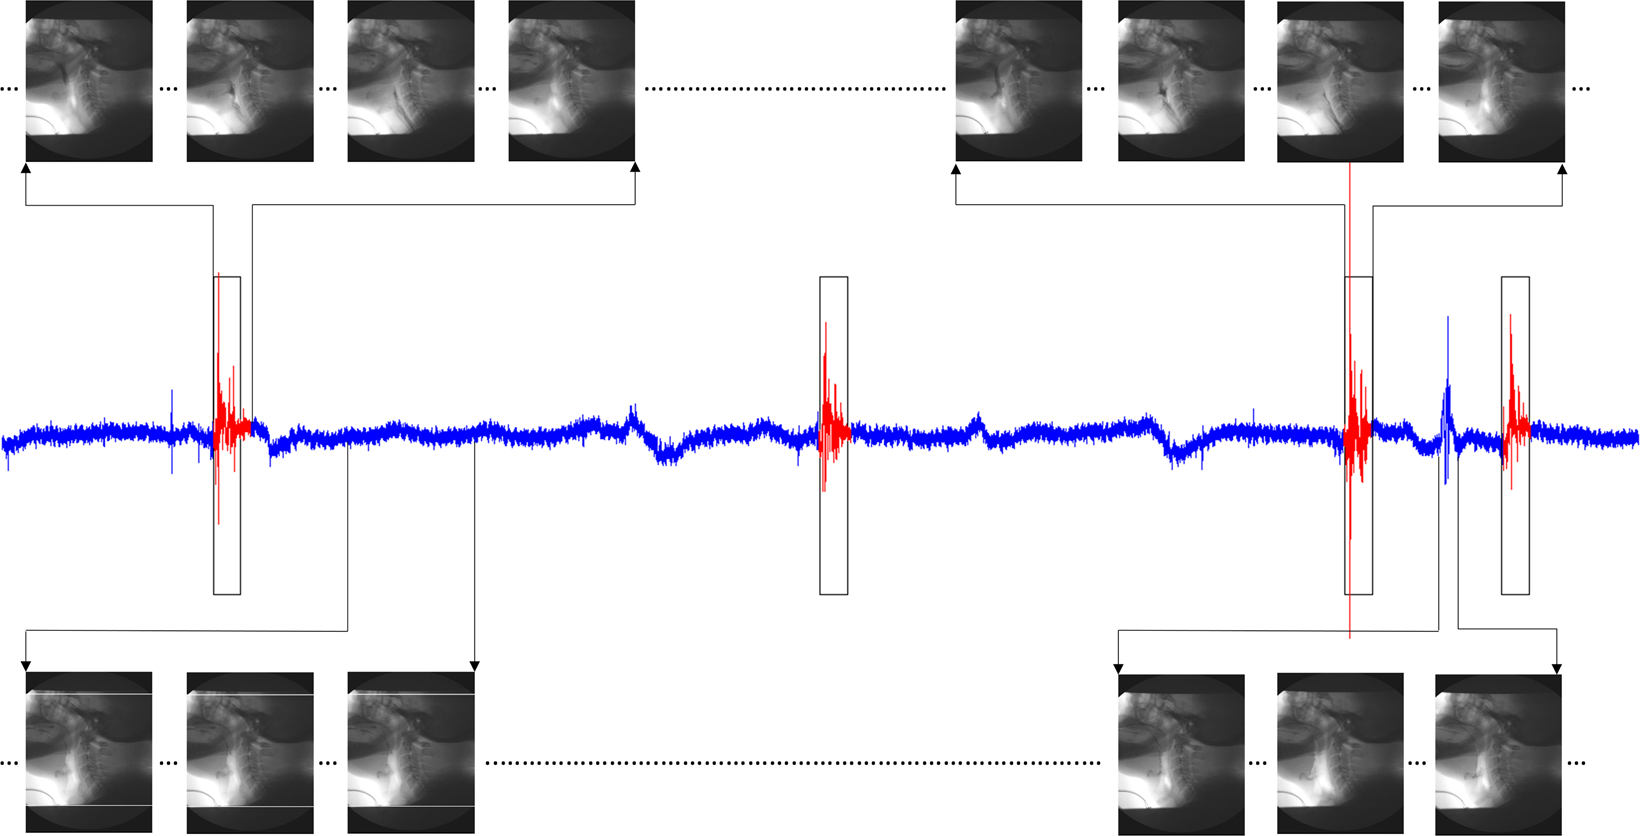

Figure 9

A clean A-P acceleration record. The red segments represent swallows as labeled by SLP. Black boxes are segments detected by the algorithm. Images on each corner are simultaneous VFSS snapshots of the signal events.